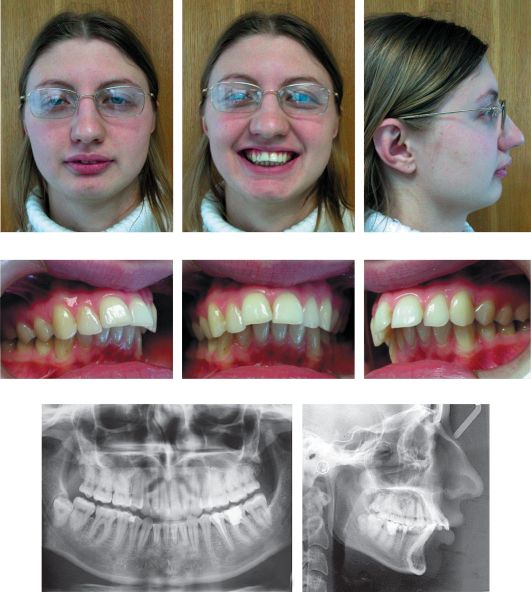

Ряд Зубов Фото